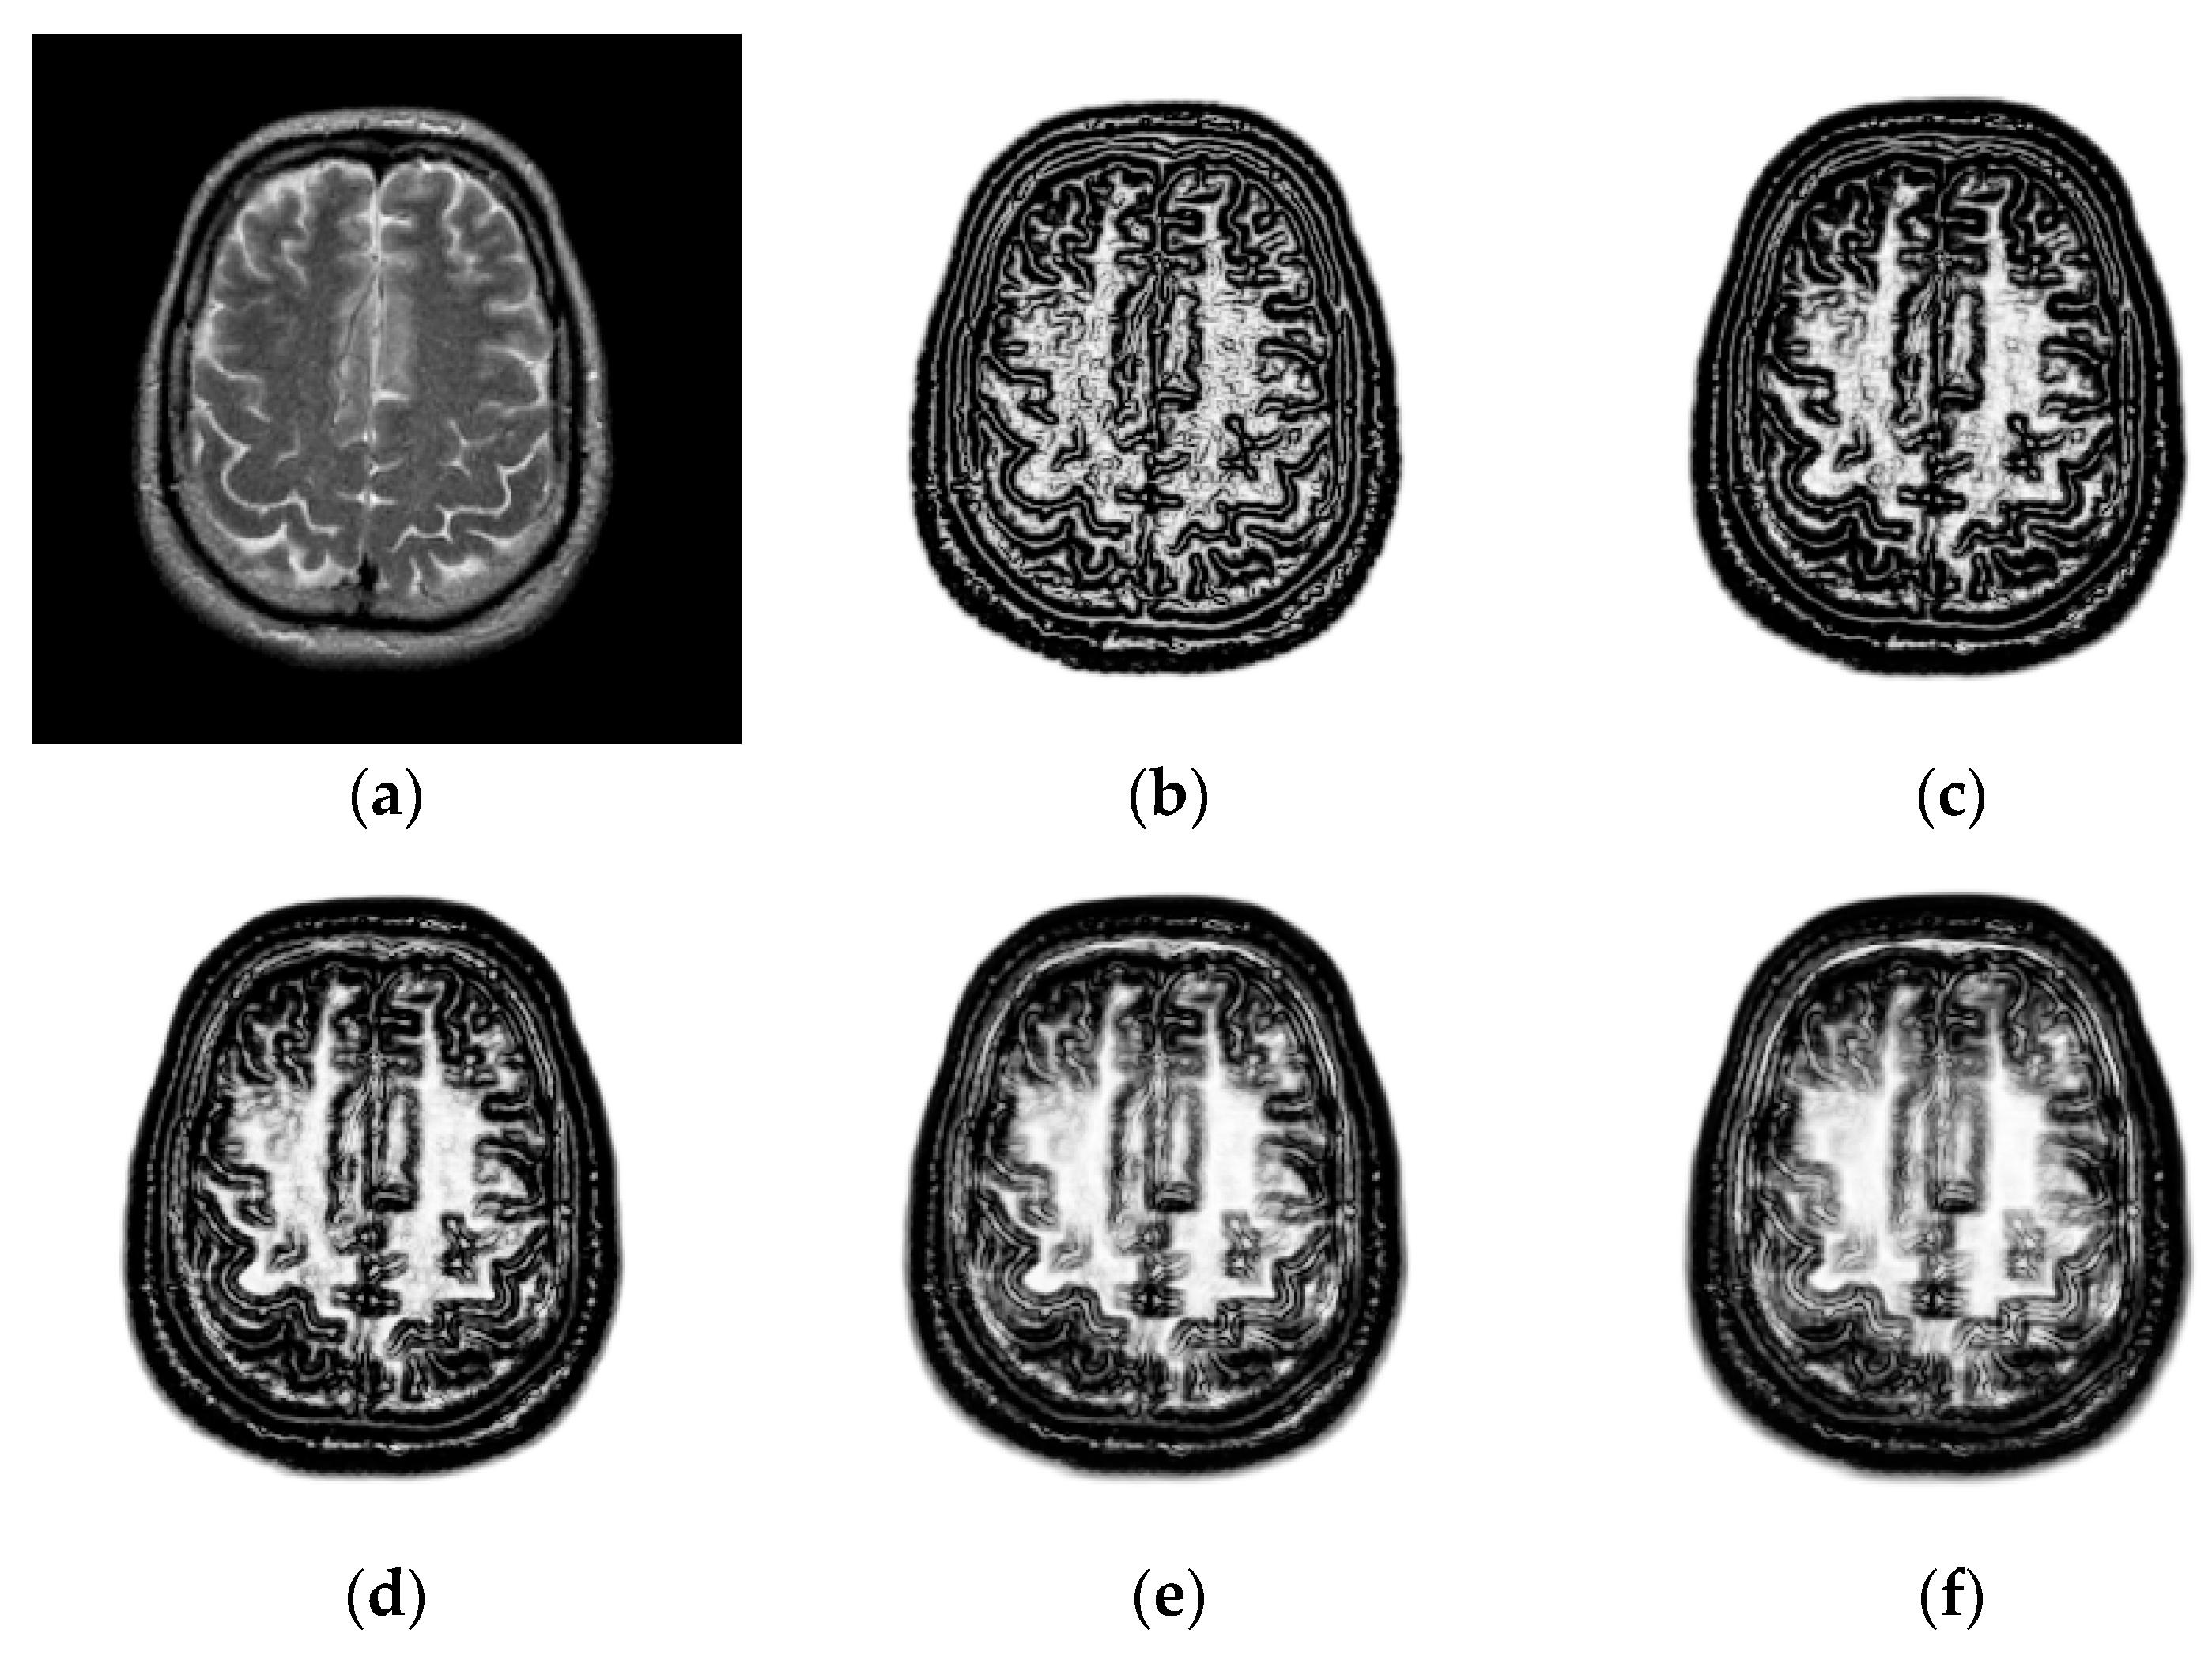

3.1.1. Impact of the Patch Size

3.1.2. Impact of the Coefficients and